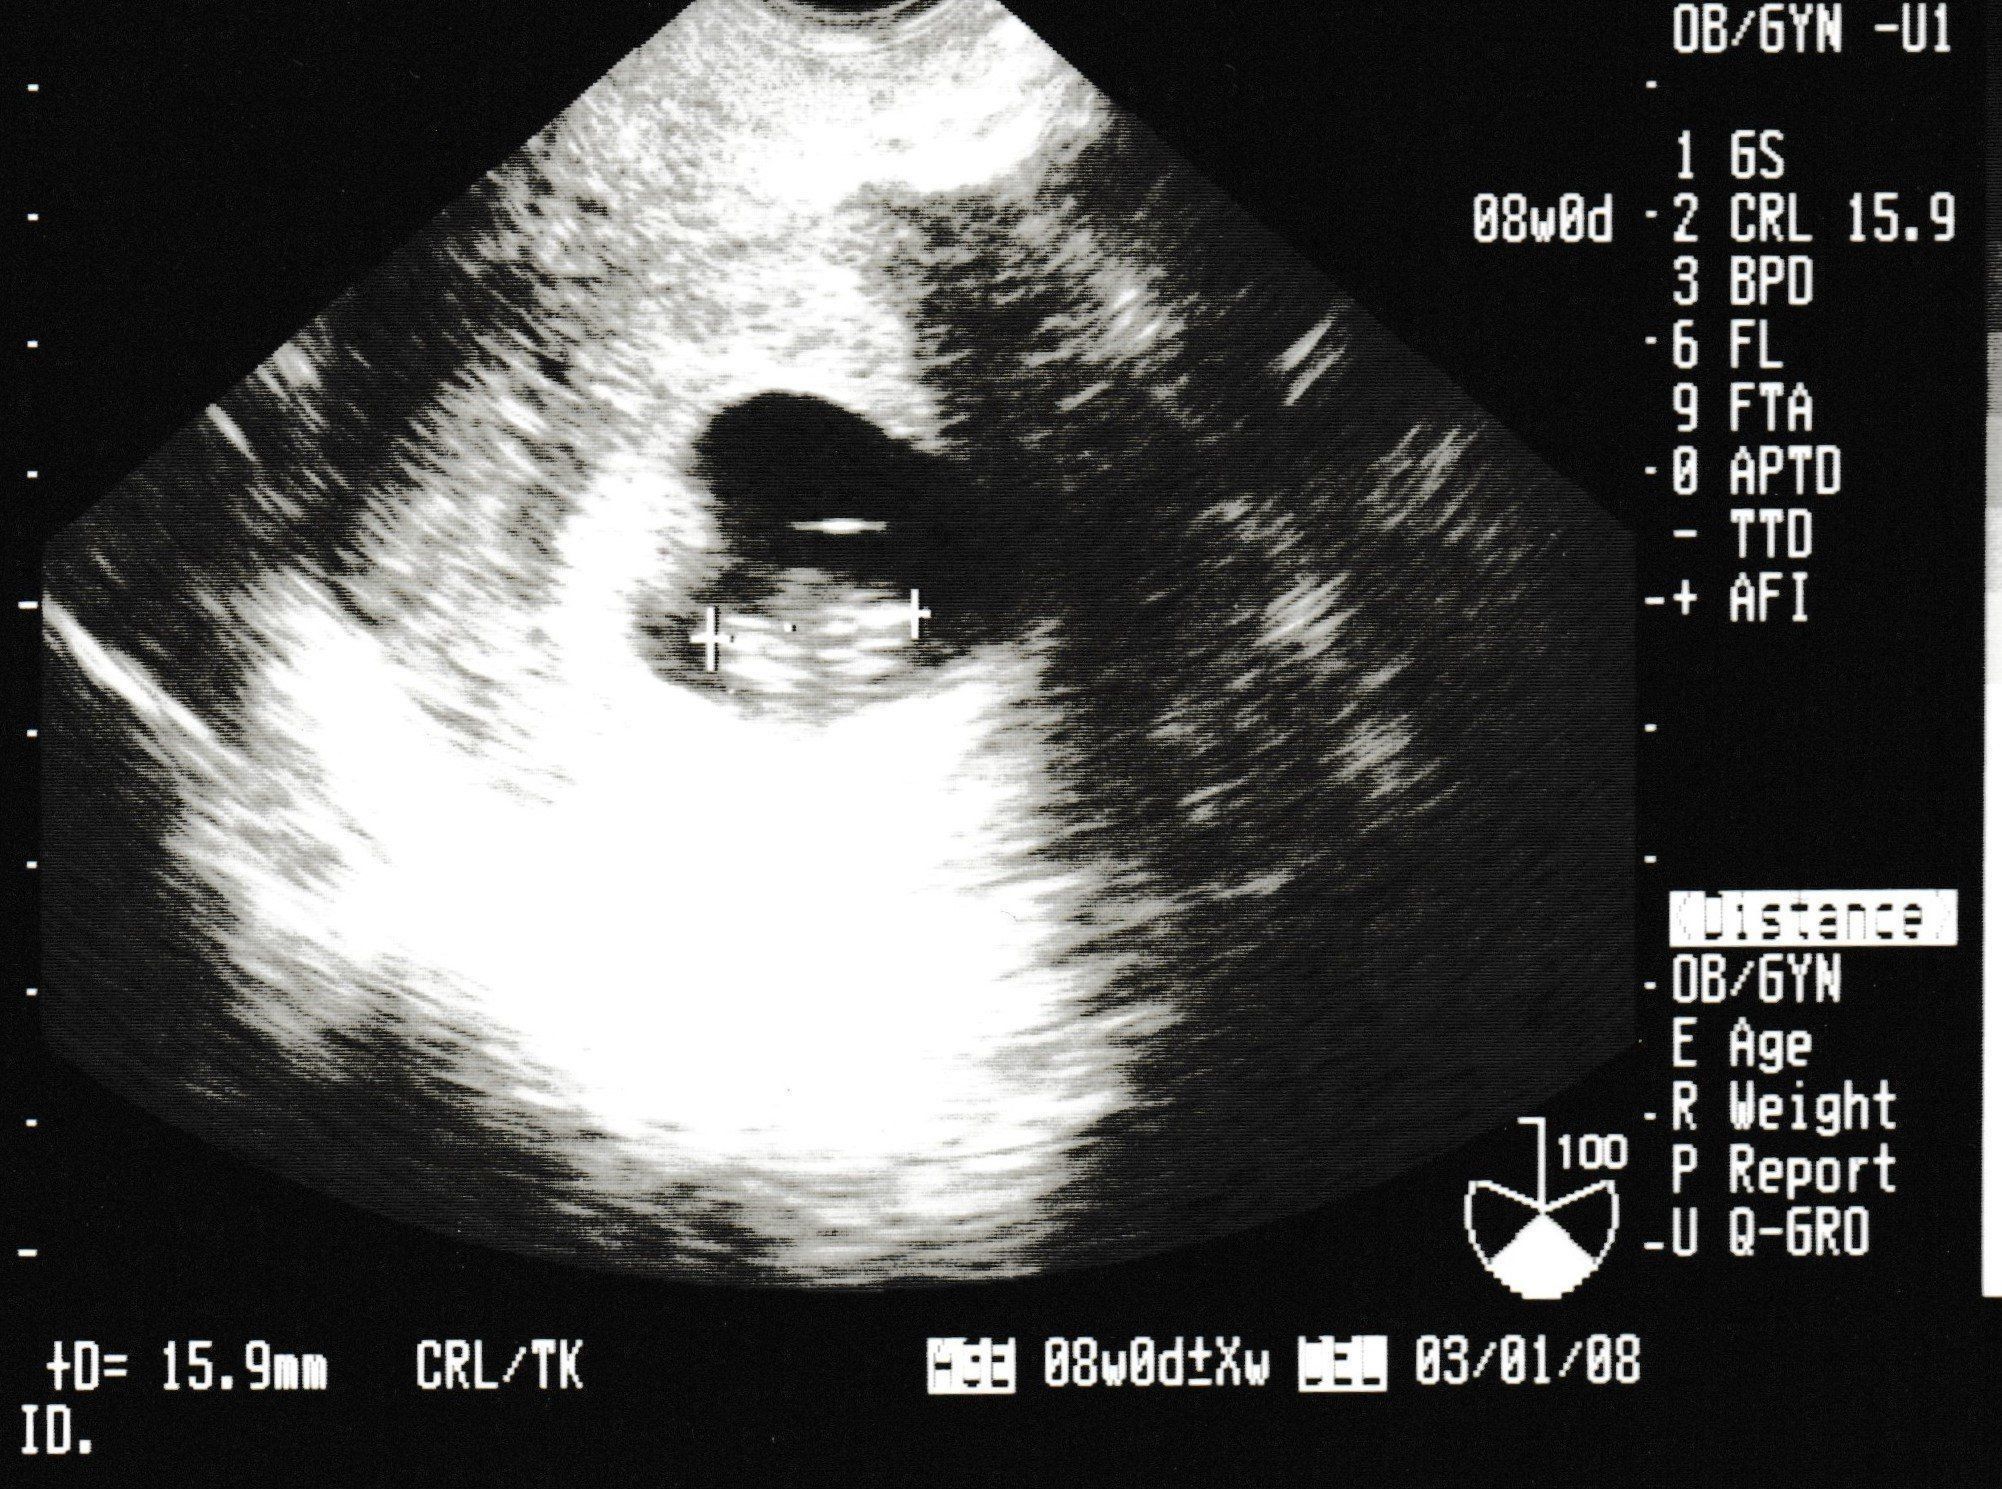

妊娠9週目のエコー写真

4D画像で頭、手、足を見ることができました。枝豆のような頭の形でなんだかかわいい、と早くも親バカ。この時期は、子宮がんや感染症の免疫の有無など、様々な検査を行いました。実母に、私がはしかやおたふく風邪にかかったかなどや、母がどのような妊娠・出産をしたかを教えてもらいました。